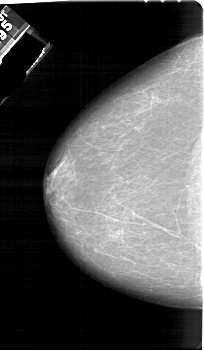

A_1161_1.RIGHT_CC

RIGHT_CC LINES 6256 PIXELS_PER_LINE 3661 BITS_PER_PIXEL 12 RESOLUTION 43.5 NON_OVERLAY